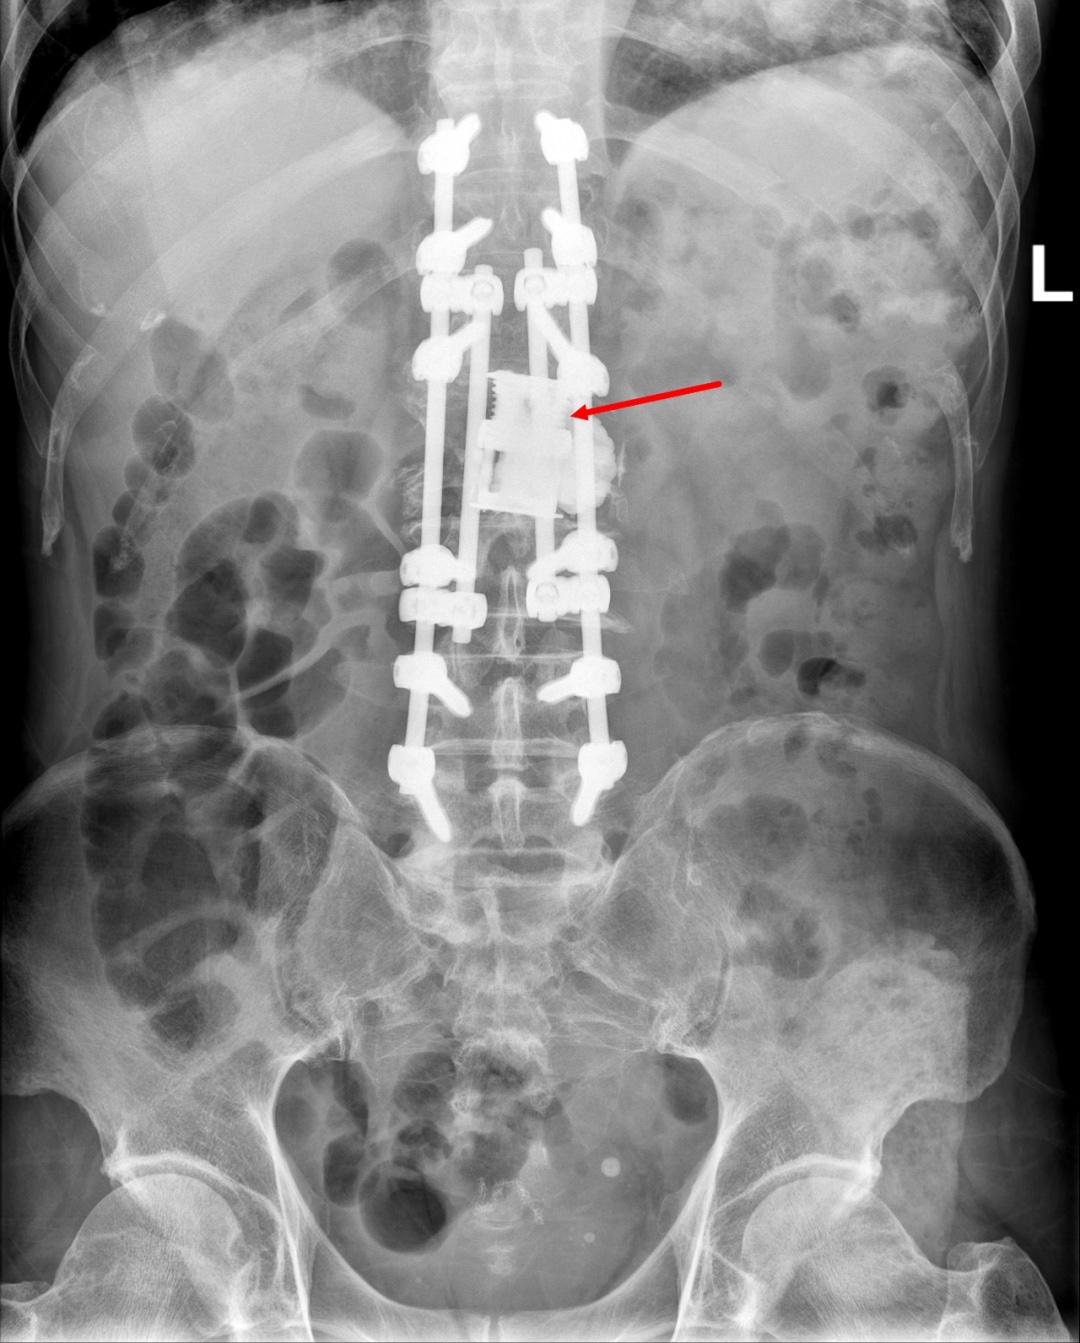

手术后

术前,为了安全起见,专家团队进行了充分的术前准备。术中,对两位患者的病变椎体进行了分离手术。为了防止术后脊柱塌陷,两节椎体之间用人工椎体支撑重建,钉棒系统固定,加强稳定性。整个手术非常顺利,术后予对症治疗后患者恢复良好。

分离手术是通过后路切除椎板和至少一侧的关节突关节,环形切除硬脊膜周围 5-8 mm 的肿瘤及后纵韧带和部分椎体,以达到对脊髓的充分环形减压,保证脊髓周围存在间隙,以便后续进行放疗术;同时取出的标本可以进行基因检测,为下一步靶向治疗提供条件。